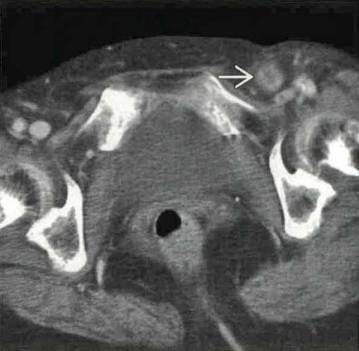

闭孔疝,腰疝,半月线疝.